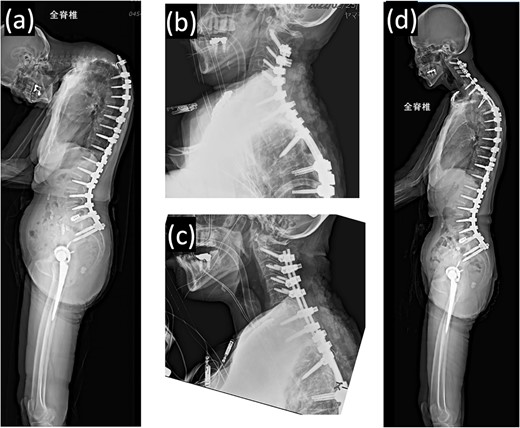

Proximal junctional kyphosis gradually developed after the initial surgery, eventually causing difficulty in maintaining a horizontal gaze 16 months post-surgery due to dropped head syndrome (Fig. 2a). A second corrective cervical spine surgery was performed 17 months post-surgery, involving extended fusion to C2 and pedicle subtraction osteotomy of T4 (Fig. 2b). The patient was extubated in the operating room immediately after the surgery and returned to the ward.

(a) Standing whole-spine radiographs 16 months after the first surgery, showing features of dropped head syndrome associated with proximal junctional failure; lateral radiographs immediately after (b) the second and (c) third surgeries; (d) standing whole-spine radiographs 16 months after the third surgery.

On postoperative Day 1, she resumed eating and drinking, but with delayed swallowing time. The wound drain was removed on postoperative Day 2, and walking exercises were initiated. Though no specific issues were noted, she exhibited signs of delirium, unclear responses, and occasional snoring-like breathing. However, on postoperative Day 6, a nurse found her bedridden, with a pale face and eyes open, drooling and snoring. The patient’s oxygen saturation was 55%; when the bed was flattened and the airway was suctioned, consciousness was restored and oxygenation improved in ~20 s. The diagnosis was obstructive dyspnea, supported by the persistence of snoring after resuming breathing. Neurological symptoms had not worsened, and intracranial lesions or cardiovascular events were deemed unlikely based on computed tomography (CT) scans, electrocardiograms, and blood test results. The rapid increase in the C2–7 angle from −15° before the second operation to 32° postoperatively led to the conclusion that a decrease in the O-C2 angle was associated with occlusive dyspnea. Emergency surgery was performed to re-fixate the cervical spine, reducing kyphosis (Fig. 2c). Postoperatively, the patient was managed on a ventilator and extubated on the second postoperative day. Sixteen months later, she experienced no further dyspnea (Fig. 2d and 3b).